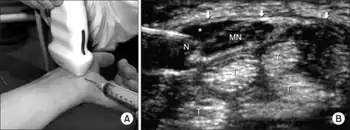

CTS work up is the most common referral to the electrodiagnostic lab. Historically, diagnosis has been made with the combination of a thorough history and physical examination in conjunction with the use of electrodiagnostic (EDX) testing for confirmation. Additionally, evolving technology has included the use of ultrasonography in the diagnosis of CTS. However, it is well established that physical exam provocative maneuvers lack both sensitivity and specificity. Furthermore, EDX cannot fully exclude the diagnosis of CTS due to the lack of sensitivity. A Joint report published by the American Association of Neuromuscular and Electrodiagostic Medicine (AANEM), the American Academy of Physical Medicine and Rehabilitation (AAPM&R) and the American Academy of Neurology defines practice parameters, standards and guidelines for EDX studies of CTS based on an extensive critical literature review. This joint review concluded median and sensory nerve conduction studies are valid and reproducible in a clinical laboratory setting and a clinical diagnosis of CTS can be made with a sensitivity greater than 85% and specificity greater than 95%. Given the key role of electrodiagnostic testing in the diagnosis of CTS, The American Association of Neuromuscular & Electrodiagnostic Medicine has issued evidence-based practice guidelines, both for the diagnosis of carpal tunnel syndrome.